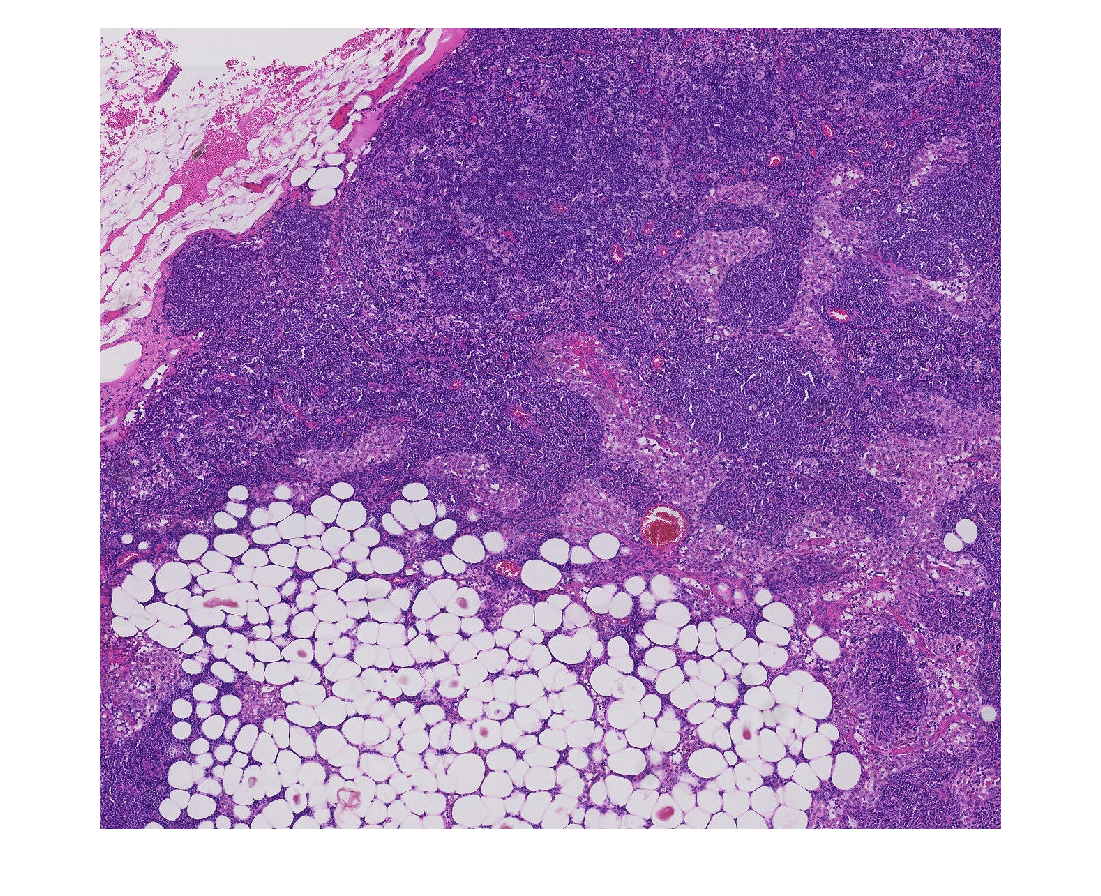

Создайте bigimage. Это примеры использует модифицированную версию изображения "tumor_091.tif" от набора данных CAMELYON16. Оригинальное изображение является учебным изображением лимфатического узла, содержащего ткань опухоли. Оригинальное изображение имеет восемь уровней разрешения, и самый прекрасный уровень имеет разрешение 53760 61440. Модифицированное изображение имеет только три крупных уровня разрешения. Пространственная ссылка модифицированного изображения была настроена, чтобы осуществить сопоставимое соотношение сторон и указать функции на каждом уровне.

Отобразите большое изображение при помощи bigimageshow функция.

bigimageshow(bim);